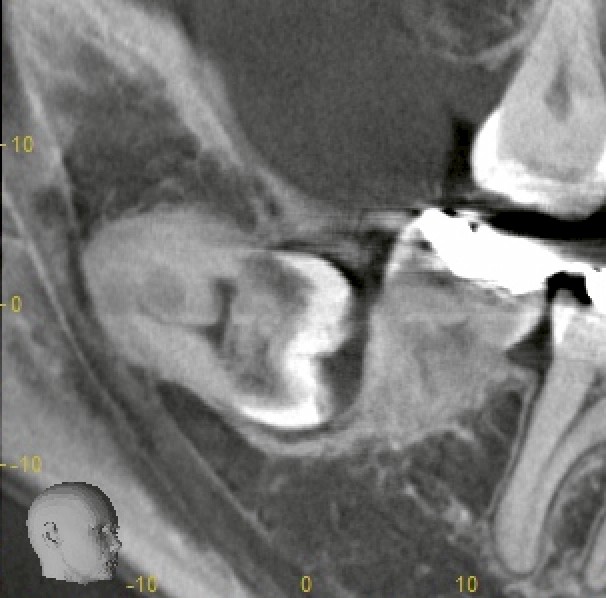

CTで確認すると、親知らずの一部が骨と癒着している状態。

長期間骨内に埋まっていた親知らずは、炎症がなくても骨とくっつくように“癒着”を起こすことがあります。

● 癒着した親知らずの特徴

* 動かない

* 分割しても割れにくい

* 周囲の骨を慎重に取り除く必要がある

* 抜歯難易度が最も高いタイプの一つ

今回も侵襲性はやや高い処置となりましたが、

ルーペで視野を確保し、周囲組織を傷つけないようミリ単位で慎重に操作し、無事に抜歯完了しました。